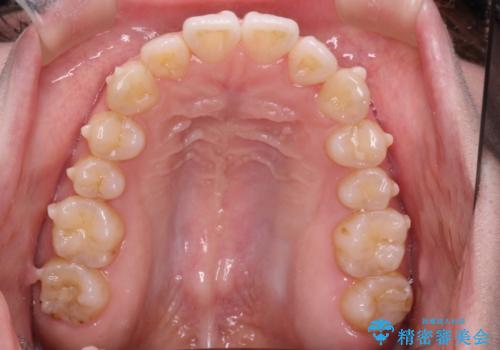

前歯にがたつきがあり、上下の歯が咬み合っていない状態でした。

歯列の横幅をひろげるのと、歯と歯の間をわずかに削ることにより、前歯のがたつきと、開咬を改善しました。